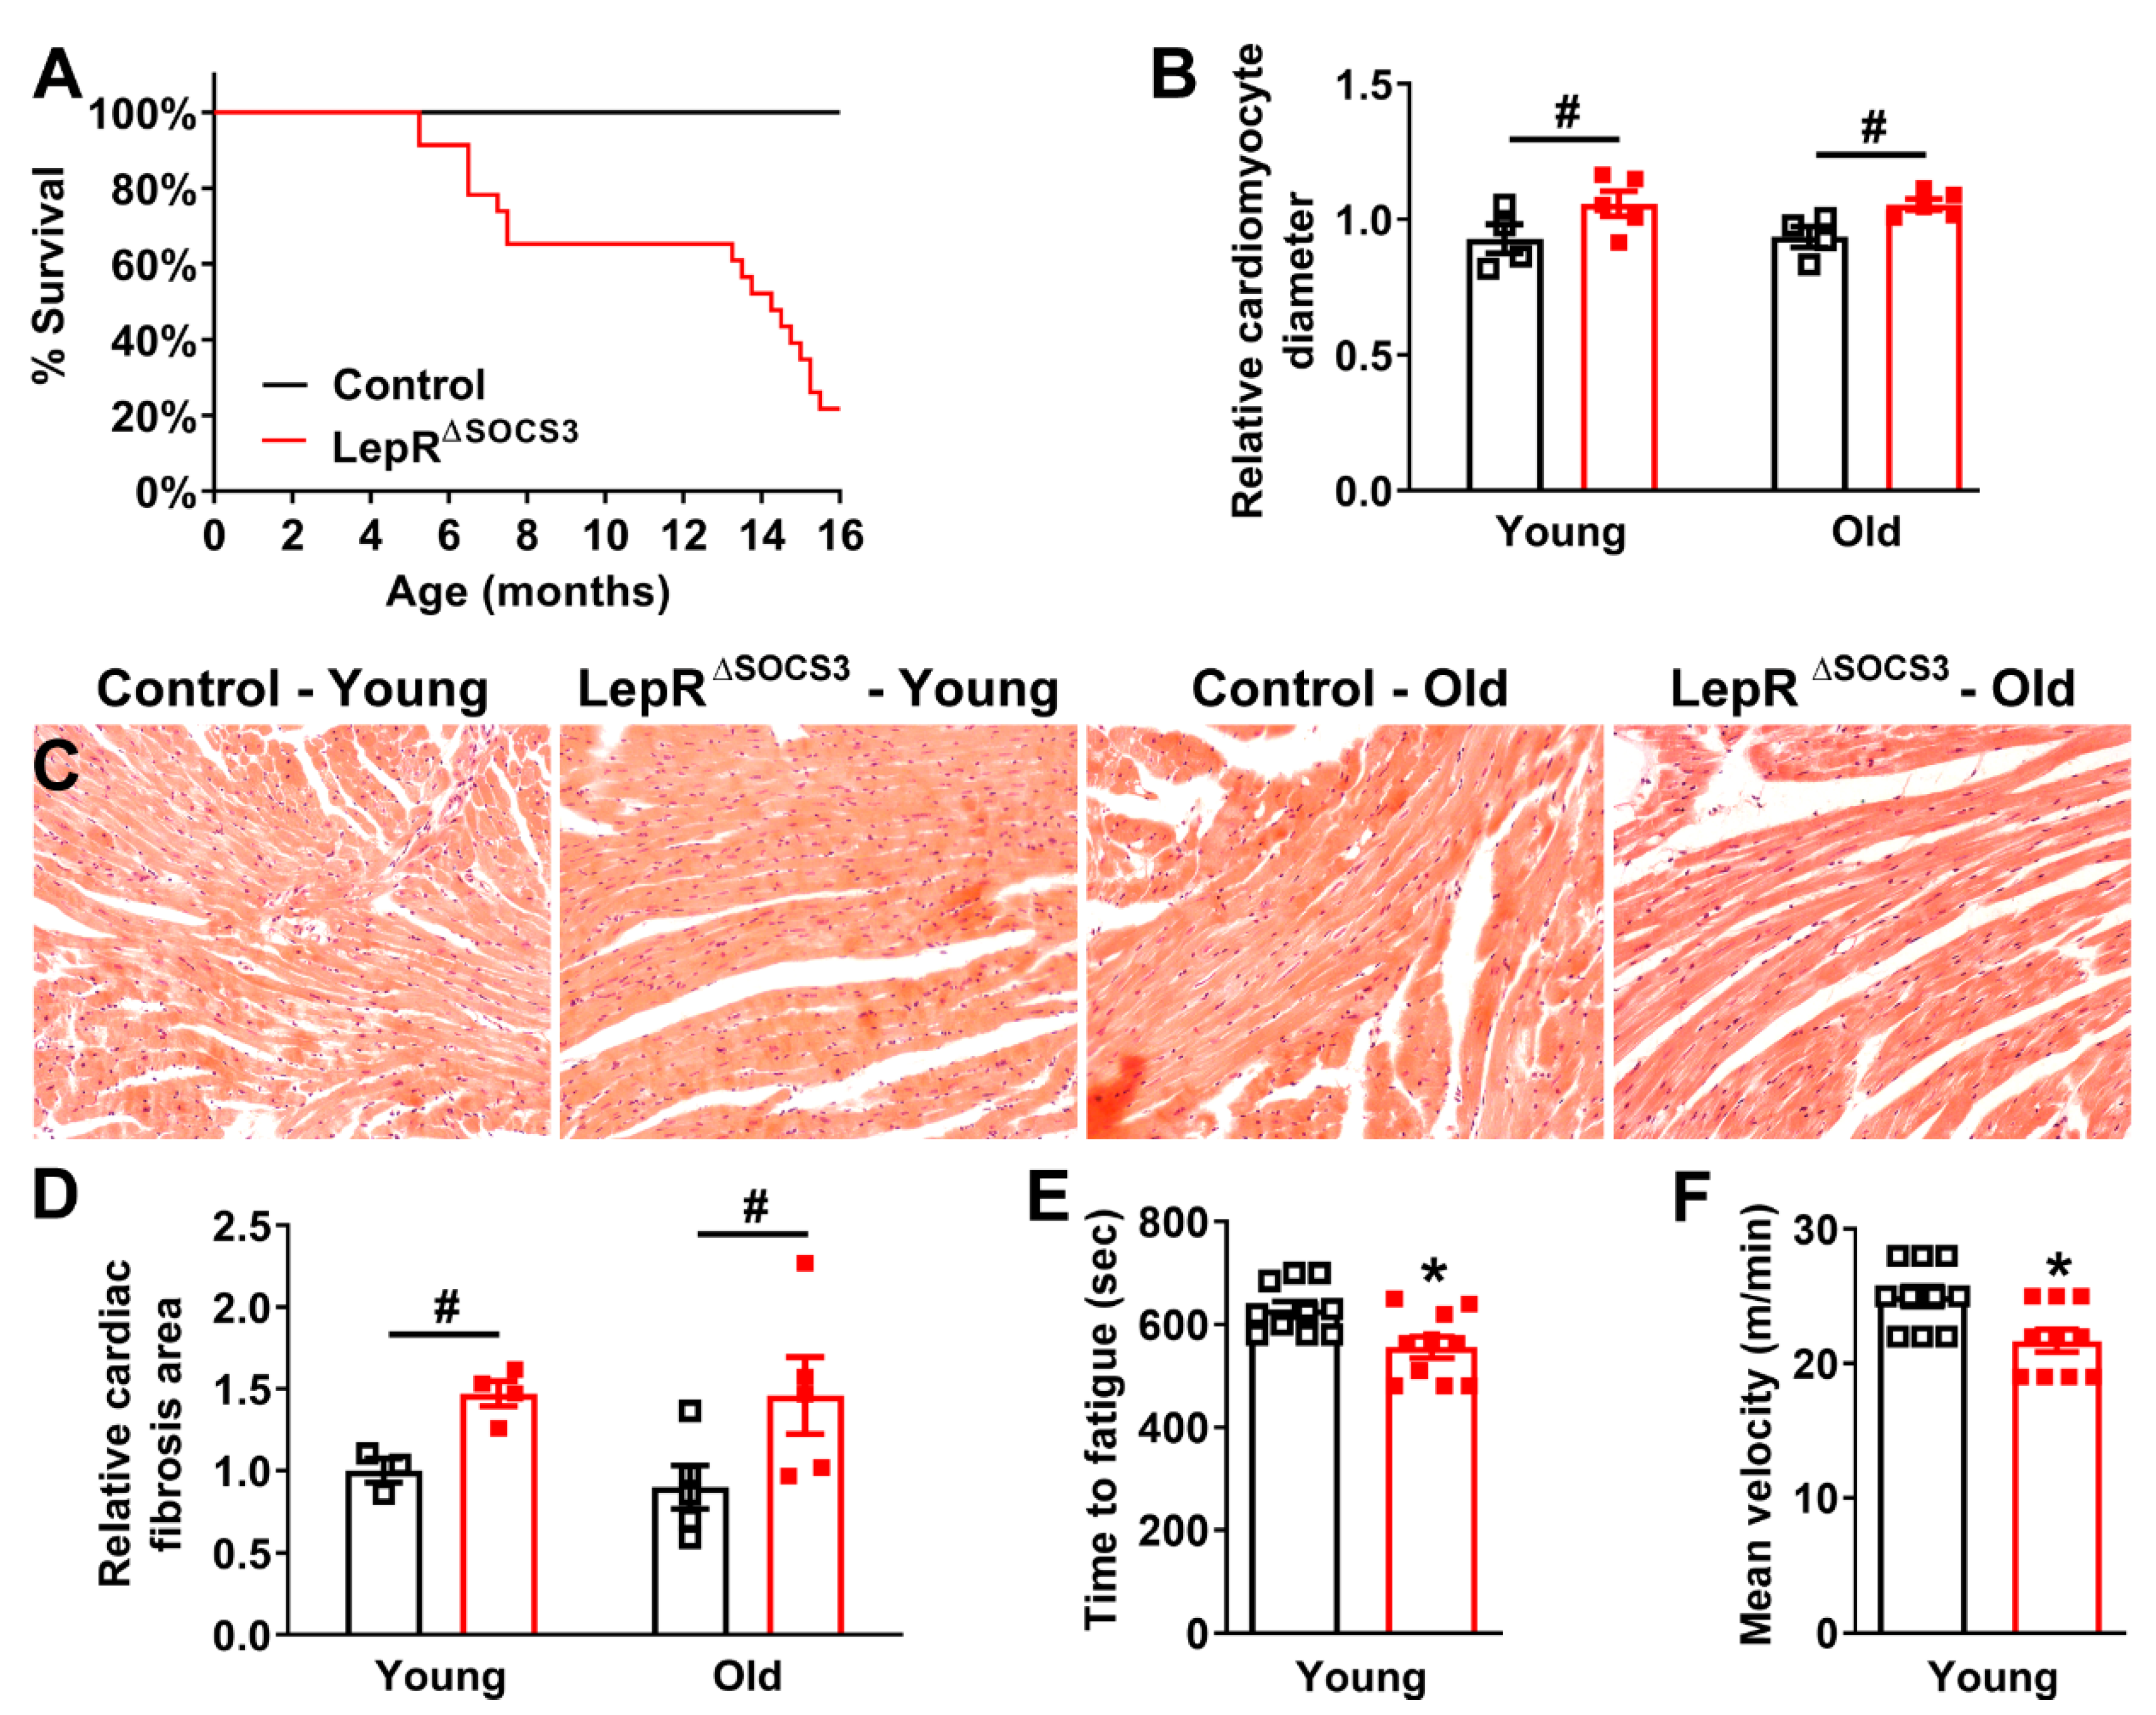

2.3. Cardiac Abnormalities and Decreased Survival Rate in Aging LepR∆SOCS3 Mice